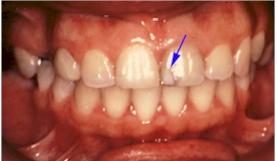

L'ouverture d'un diastème révélé par l'interrogatoire a peut être pour étiologie une dysfonction.